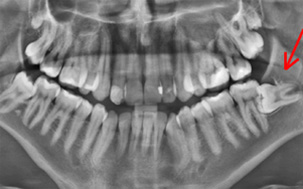

Στα πλαίσια της ορθοδοντικής θεραπείας συχνά απαιτείται συνεργασία με τον γναθοχειρουργό. Τέτοιες περιπτώσεις είναι η εξαγωγή δοντιών με αυξημένο βαθμό δυσκολίας, αφαίρεση εγκλείστων φρονιμιτών, αντιμετώπιση κύστεων ή/και αποκάλυψη δοντιών που για κάποιους λόγους είναι έγκλειστα μέσα στο κόκαλο της γνάθου.

Η συνεργασία ορθοδοντικού και γναθοχειρουργού είναι απαραίτητη στην περίπτωση ενηλίκων ασθενών με έντονη σκελετική ανωμαλία. Ο ορθοδοντικός θα διευθετήσει την θέση των δοντιών στην κάθε γνάθο (προχειρουργική ορθοδοντική θεραπεία) και όταν αυτό ολοκληρωθεί ο γναθοχειρουργός με την κατάλληλα σχεδιασμένη επέμβαση (γναθοχειρουργική επέμβαση) θα διευθετήσει το μέγεθος και την σχέση των γνάθων μεταξύ τους. Τέλος ο ορθοδοντικός θα προχωρήσει (μεταχειρουργική ορθοδοντική) στις τελικές μικρομετακινήσεις ακριβείας των δοντιών. Αυτό το μεικτό σχήμα θεραπείας είναι απαραίτητο για ένα καλό και σταθερό αποτέλεσμα.